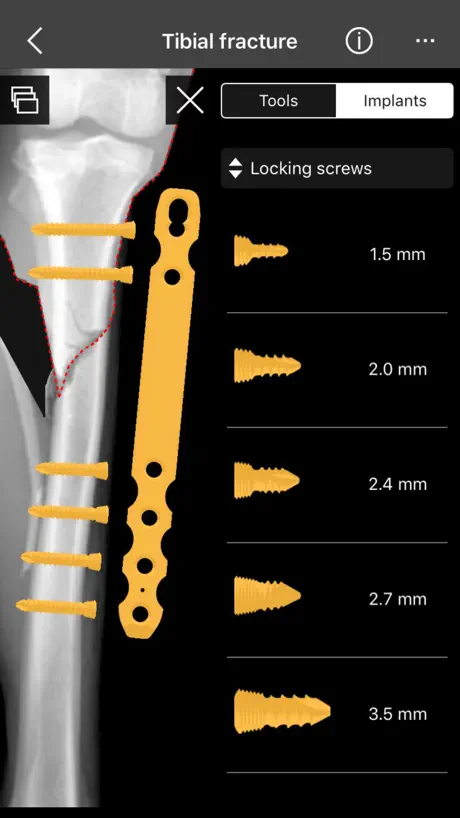

4. Catalogue of BETA Implants locking plates, in 2.0, 2.4, 2.7 and 3.5 sizes:

o) Locking screws

4. Catalogue of BETA Implants locking plates, in 2.0, 2.4, 2.7 and 3.5 sizes:

o) Locking screws